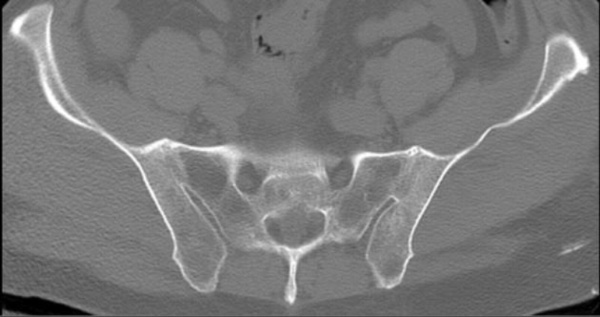

Sau đây là một số hình ảnh viêm cột sống dính khớp trên X-quang: